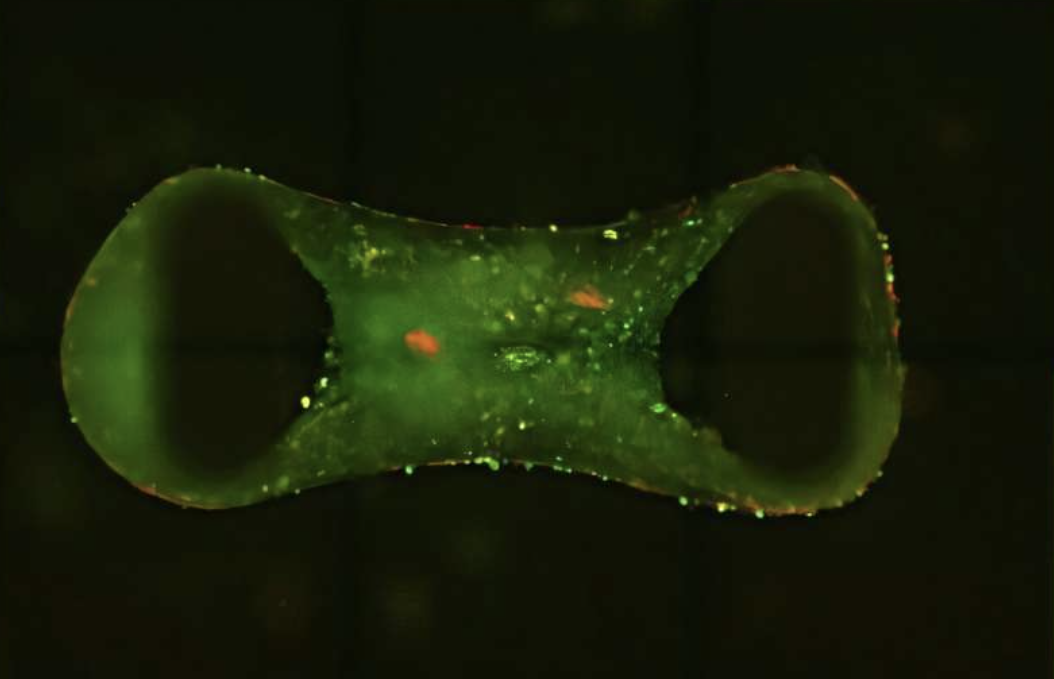

QIMR Berghofer’s Cardiac Bioengineering Lab இனைச் சேர்ந்த விஞ்ஞானிகள் மனிதனின் உண்மையான இதயத்தின் கட்டமைப்பையும், இயக்கத்தையும் அப்படியே பிரதிபலிக்கும் முப்பரிமான திசுக்களால் ஆன இதயத்தை உருவாக்கியுள்ளனர். Cardiac Organoids என இந்த திசுக்கள் அழைக்கப் படுகின்றன.

இந்த திசுக்களை உருவாக்க விஞ்ஞானிகள் human pluripotent stem cells எனப்படும் விசேட கலங்களைப் பயன்படுத்தியுள்ளனர். இந்த விசேட கலங்கள் மனித உடலிலுள்ள எந்த உறுப்பினதும் கலங்களாகவும் மாற்றமடையக் கூடியது என்பது குறிப்பிடத்தக்கது. இருப்பினும், இந்த ஸ்டெம் செல்கள் இதய செல்களாக மாறும்போது, அவை பொதுவாக முதிர்ச்சியடையாமல் இருக்கும், மேலும் வளரும் குழந்தையின் இதய திசுக்களைப் போலவே இருக்கும். இந்த முதிர்ச்சியின்மை குழந்தை பருவத்திலோ அல்லது பெரியவர்களாகவோ இருக்கும் போது தோன்றும் மாதிரி நோய்களுக்கு எதிராக அவற்றின் பயன்பாட்டைக் கட்டுப்படுத்தலாம்.

QIMR பேராசிரியர் ஜேம்ஸ் ஹட்சன் கூறுகையில், ‘சிறிய இதயங்கள் ஒரு சியா விதையின் அளவாக இருக்கலாம், ஆனால் புதிய சிகிச்சைகளைக் கண்டறிய ஒரு தளத்தை வழங்குகின்றன. “இந்த வழியில் இதய நோய்களைப் படிப்பதில் ஒரு பெரிய நன்மை இருக்கிறது. மனித இதய ஆர்கனாய்டுகளைப் பயன்படுத்துவது இன்னும் பல சேர்மங்களைத் திரையிட அனுமதிக்கிறது, மருந்து வளர்ச்சியின் செயல்முறையை விரைவுபடுத்துகிறது.’ என்றுள்ளார்.